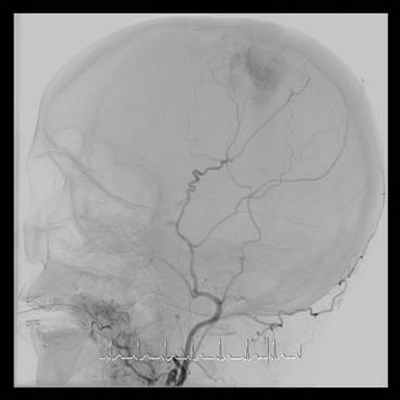

Ротационная ангиография артерий головного мозга (22.10.15): выявлено кровоснабжение менингиомы из бассейнов правой и левой наружной и левой внутренней сонных артерий.

28.10.2015 была выполнена операция: эндоваскулярная эмболизация микроэмболами ветвей обеих наружных сонных артерий, питающих опухоль.

Катетер установлен в левую бедренную артерию. Выполнена серия ангиограмм. При помощи микрокатетера поэтапно кататеризированы эмболизированы микроэмболами вначале слева, а затем справа питающие опухоль сосуды. На контрольных ангиограммах кровотока по данным артериям не выявлено, опухоль не кровоснабжается.

Выявление питающих опухоль сосудов

Состояние после эмболизации – кровенаполнения опухоли не выявлено